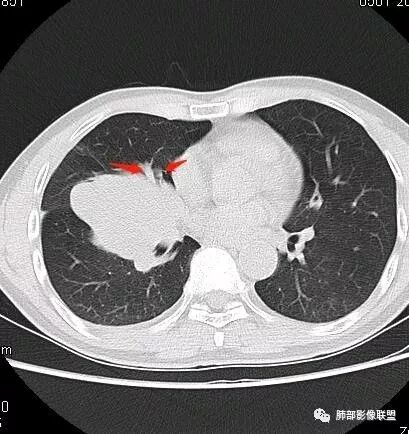

初学者:如果中叶病灶,叶间裂应该下推,也不会上推

南边:从叶裂的变形,下朝上,越来越朝前扭曲,提示叶裂局部有朝前上推移的趋势

南边:下叶的支气管受压后移、变形

南边:病灶边界清,提示侵袭性弱,膨胀生长为主;这时候我们提示病灶不应该是支气管关系密切,提示间叶来源或胸膜来源

深分叶,警惕恶性

常规考虑:1、肉瘤首先考虑

2、胸膜孤立性纤维瘤待排

南边:结果:肉瘤